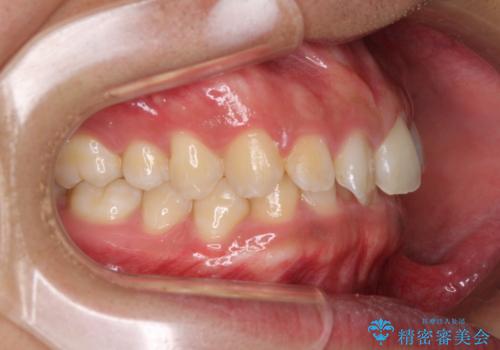

デコボコとディープバイトを治したい インビザラインによる矯正治療

- 前歯のデコボコや隙間と深い咬み合わせ(ディープバイト)を気にして来院された患者様です。

インビザラインによる上下歯列の側方拡大と後方移動、IPR(歯と歯の間を削る)にるスペースの獲得により、デコボコとディープバイトを改善することとしました。

気になっていたデコボコや隙間は改善し、きれいな歯列に整えることができました。

咬合力が非常に強い方であったため、これ以上のディープバイトの改善は困難となりました。